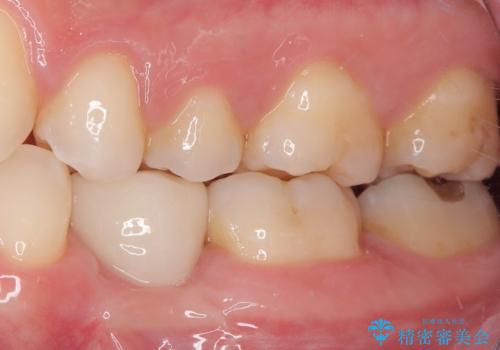

永久歯の先天欠如 インプラントによる補綴

義歯と違ってしっかり噛めるようになって食事がおいしくなったと満足していただけました。